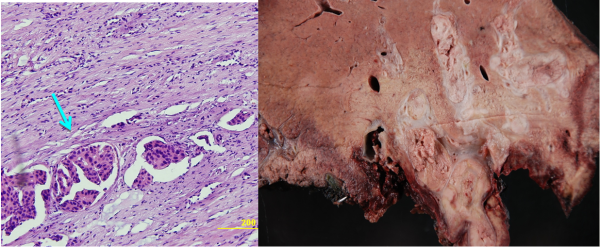

מבחינה פתולוגית שאתות אלה מופיעות לרוב כנגע בודד גדול נודולרי או כנגעים מרובים על פני הכבד כולו. ב- FLC הנגעים בדרך כלל בודדים (75%) ממוקמים באונה שמאלית בעיקר. שאתות ה- HCC הן בעלות מבנה טרבקולרי ועשירות בכלי דם ולעיתים קרובות פולשות לענפים של הווריד הפורטלי ואף לענפים של ורידי הכבד (תמונה 9.10).

- בדרך כלל אין צורך בביופסיה מחטית של הנגע בתנאי שניתן לראות ב- CT מאפיינים קלאסיים ל- HCC. כיוון שה- HCC היא שאת מאוד וסקולרית הרי שהיא "נצבעת" מהר וחזק בשלב ההזרקה ויש שטיפה מהירה בשלב הפורטלי המאוחר (תצלום 30.10-33.10).

| תצלום 32.10: HCC החודרת לכלי דם ויוצרת קרישים בכלי דם ורידיים. | |

|---|---|